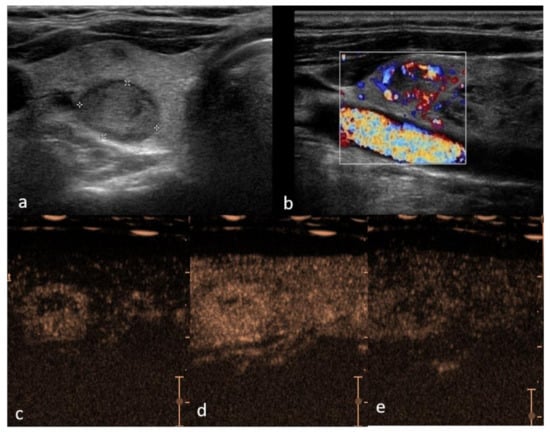

Figure 1. Right lobe hypoechoic lesion with halo sign, TIRADS 3, Bethesda 2, Follicular hyperplasia (a)—B mode hypo-echogenicity of the structure; (b) color Doppler shows hypervascularity in peripheral part of the lesion; (c) contrast enhancement is predominantly peripheral with smooth ring enhancement, with areas of rapid and intense vascularization in periphery and slow in the center (d) and suggestive slow wash-out (e) in comparison to the adjacent parenchyma.

Thyroid adenoma is a benign lesion with morphologically follicular or papillary architecture [72]. Adenomas may be hormonally active causing hyperthyroidism, also known as toxic adenomas, or appear inactive [72]. Cytologic features between follicular adenoma, carcinoma and follicular variants of papillary carcinoma overlap, suggestive of the difficult differential diagnosis [73], and pathological examination is required [74]. Jiang et al. conducted a study in which thyroid adenomas were analyzed by CEUS and mainly presented with a homogenous hyperenhancement; this is due to the fact that adenomas have a complete capsule with surrounding rich blood supply [36], as they mainly grow expansively, gradually pushing the arteries and veins towards the periphery of the tumor, with the continuous growth of new capillaries. Therefore, the contrast agent reaches the center of the nodule more slowly compared with the normal surrounding tissue and wash-out is equally slow, displaying a “fast-in and slow-out” imaging pattern (Figure 1). In a study by Schleder et al. CEUS was used in a preoperative setting to differentiate thyroid adenoma vs. carcinoma in a total of 101 patients. A statistically significant difference in microcirculation between adenoma and carcinoma was noted; adenoma was characterized by no wash-out or wash-out with a persisting edge in the late phase; in contrast, thyroid carcinomas showed a complete wash-out in the late phase with CEUS sensitivity, specificity, PPV and NPV of 81%, 92%, 97% and 63%, respectively [75].